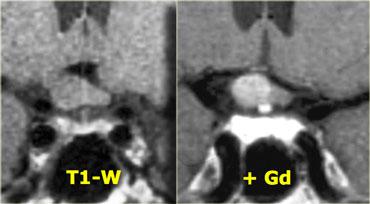

Trên các hình ảnh trên, có thể thấy tuyến yên bình thường, giao thoa thị giác bình thường và động mạch cảnh bình thường ở mỗi bên.

Tuy nhiên, cuống tuyến yên không thể xác định được do có một khối tròn ở vùng này.

Khối này có tín hiệu cao trên chuỗi xung T1W không tiêm thuốc tương phản từ.

Chỉ có hai thành phần cho tín hiệu sáng như vậy trên chuỗi xung T1W không tiêm thuốc tương phản từ, đó là: dịch (máu hoặc dịch giàu protein) hoặc mỡ.

Các khối đặc không có tín hiệu sáng như vậy.

Do đó, nhiều khả năng đây là một cấu trúc dạng nang có nguồn gốc từ cuống tuyến yên, có thể là nang khe Rathke.

Sọ hầu bào dạng nang cũng nằm trong chẩn đoán phân biệt.

Các hình ảnh này minh họa tầm quan trọng của chuỗi xung T1W không tiêm thuốc tương phản từ.

Chúng cho phép xác định rằng bất thường chỉ khu trú tại cuống tuyến yên.

Nếu chỉ xem các hình ảnh sau khi tiêm thuốc tương phản từ tĩnh mạch, có thể nhầm lẫn rằng bản thân tuyến yên cũng bất thường.

Các chuỗi xung T1W, T2W và T1W sau tiêm gadolinium này minh họa một nang khe Rathke khác nằm trong tuyến yên.

Khác với mô tuyến yên bình thường và cuống tuyến yên, nang không ngấm thuốc sau khi tiêm thuốc tương phản từ tĩnh mạch.

Mô tuyến yên bình thường bị chèn ép và đẩy lệch sang bên trái. Điều quan trọng là cần nhận biết điều này vì có thể nhầm lẫn với thành phần ngấm thuốc của khối dạng nang.

Nhìn chung, tất cả các khối ngoài trục, tức là các khối nằm ngoài não như tuyến yên và cuống tuyến yên, đều sẽ ngấm thuốc vì chúng không có hàng rào máu-não.

Nếu gặp một khối ngoài trục không ngấm thuốc, có ba khả năng:

- Dòng chảy động mạch nhanh (ví dụ: mạch máu lớn).

- Không có mô tế bào (ví dụ: nang).

- Không có nguồn cung cấp máu (ví dụ: khối bị nhồi máu).